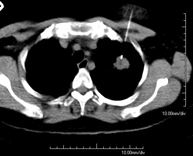

- TC Tòrax

Prova diagnòstica que consisteix en obtenir imatges del tòrax d'alta definició anatòmica (pulmons, cor, mediastí, grans vasos, caixa toràcica, etc. ) mitjançant l'ús d'un equip de TC (Tomografia Computeritzada). Aquestes imatges s'estudien posteriorment en una estació de treball que permet reconstruccions bidimensionals en diferents plànols de l'espai i també reconstruccions 3D (volumètriques). Alguns estudis requereixen l'ús de contrast iodat per millorar la definició de les imatges. - Angio –TC Aorta toràcica